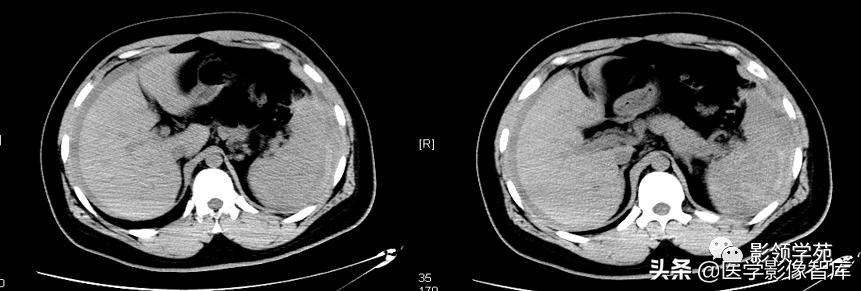

增强扫描:动脉期脾脏呈斑片状不均匀强化,静脉期及平衡期强化密度逐渐均匀。